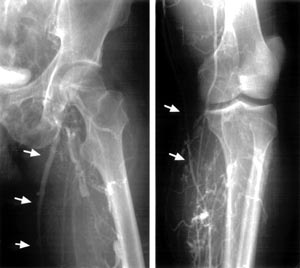

| Fig. 2 Preopeative venography. →: left great saphenous

vein |